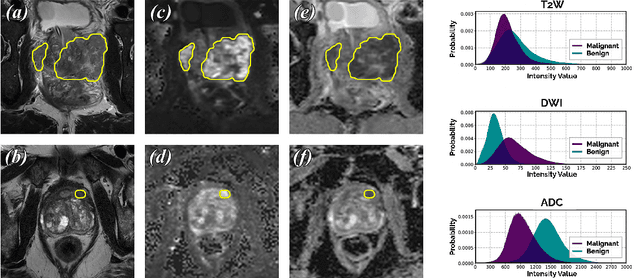

Abstract:Diffusion-based models for text-to-image generation have gained immense popularity due to recent advancements in efficiency, accessibility, and quality. Although it is becoming increasingly feasible to perform inference with these systems using consumer-grade GPUs, training them from scratch still requires access to large datasets and significant computational resources. In the case of medical image generation, the availability of large, publicly accessible datasets that include text reports is limited due to legal and ethical concerns. While training a diffusion model on a private dataset may address this issue, it is not always feasible for institutions lacking the necessary computational resources. This work demonstrates that pre-trained Stable Diffusion models, originally trained on natural images, can be adapted to various medical imaging modalities by training text embeddings with textual inversion. In this study, we conducted experiments using medical datasets comprising only 100 samples from three medical modalities. Embeddings were trained in a matter of hours, while still retaining diagnostic relevance in image generation. Experiments were designed to achieve several objectives. Firstly, we fine-tuned the training and inference processes of textual inversion, revealing that larger embeddings and more examples are required. Secondly, we validated our approach by demonstrating a 2\% increase in the diagnostic accuracy (AUC) for detecting prostate cancer on MRI, which is a challenging multi-modal imaging modality, from 0.78 to 0.80. Thirdly, we performed simulations by interpolating between healthy and diseased states, combining multiple pathologies, and inpainting to show embedding flexibility and control of disease appearance. Finally, the embeddings trained in this study are small (less than 1 MB), which facilitates easy sharing of medical data with reduced privacy concerns.